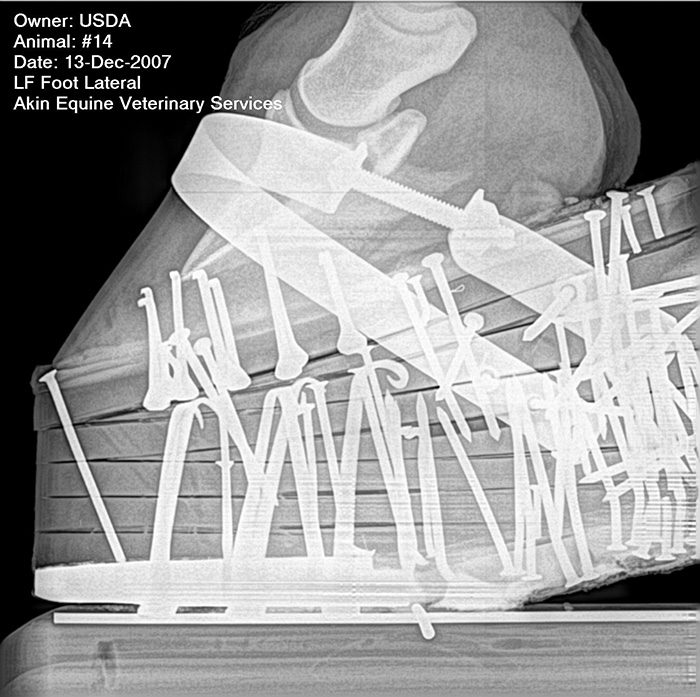

Some 49 nails were used to hold the pads together on this Tennessee Walking Horse. Equine veterinarian Tracy Turner says this is clearly excessive when you look at how the nail locations were used to add weight in the heel area. While the Horse Protection Act prohibits weights attached to the outside of the hoof wall, horseshoe or any portion of the pad, it is not clear whether this use actually constitutes a violation.